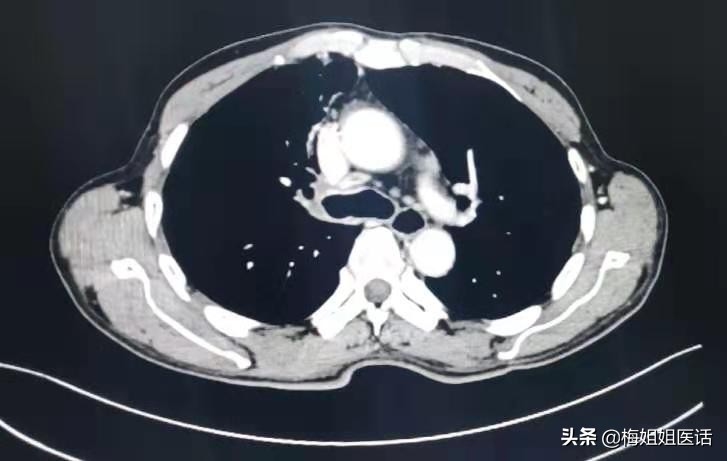

现实中,话说近日病房出院的肺癌患者,正好65岁,患者因“右胸背痛、咯血”入院,经过一系列检查,诊断右肺中央型鳞癌。

肺癌治疗前

肺癌治疗后

患者虽然年纪偏大,但心态乐观,治疗积极,家属给力,评估身体指标后难以外科手术治疗。选择行全身化疗。

化疗3个周期。胸痛咯血症状消失,态势一天比一天好。才复查评估前期治疗疗效。可以看到治疗后病变明显好转(红圈里的肿瘤几乎消失了)。病情缓解。